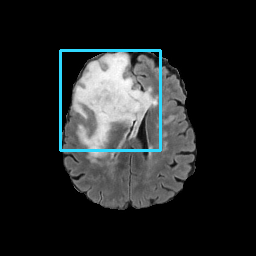

Refer to caption

(a) CT images.

(b) MRI images.

Figure 6: Lossy compression based attack on CT images (a) and MRI images (b) with a specific channel numbers (C8050\mathrm{C^{50}_{80}}) for the EP and IT Scenarios. StolenEPD1\mathrm{Stolen}^{\mathrm{D1}}_{\mathrm{EP}} denotes the decompressed images in the EP Scenario with a reduced D1 decoder.

Compression-Fidelity Compromise. Based on the previous results, we have selected the decoder D1D1 and the configuration of the latent and hyperlatent variables C8050\mathrm{C^{50}_{80}}, as the optimal architecture of the HiFiC encoder-decoder pair. In Fig. 6, we display more specifically the compression and reconstruction quality performances. In terms of reconstruction quality, we obtain a PSNR of approximately 40 for CT images and around 38 for MRI images while the MS_SSIM values are close to 1. This indicates an excellent perceptual quality of the reconstructed images that are hardly discernible from the original ones. In terms of compression efficiency, the Pratio\mathrm{P}_{\mathrm{ratio}} for CT images is approximately 0.015, indicating that the lossy image compression-based attack generated compressed images are 67 times smaller than those produced by the lossless zipped image compression-based attack. For MRI images, the Pratio\mathrm{P}_{\mathrm{ratio}} is around 0.12, 10 times higher than that of CT images, which can be attributed to the presence of a large uniform background in the skull-stripped original MR images.